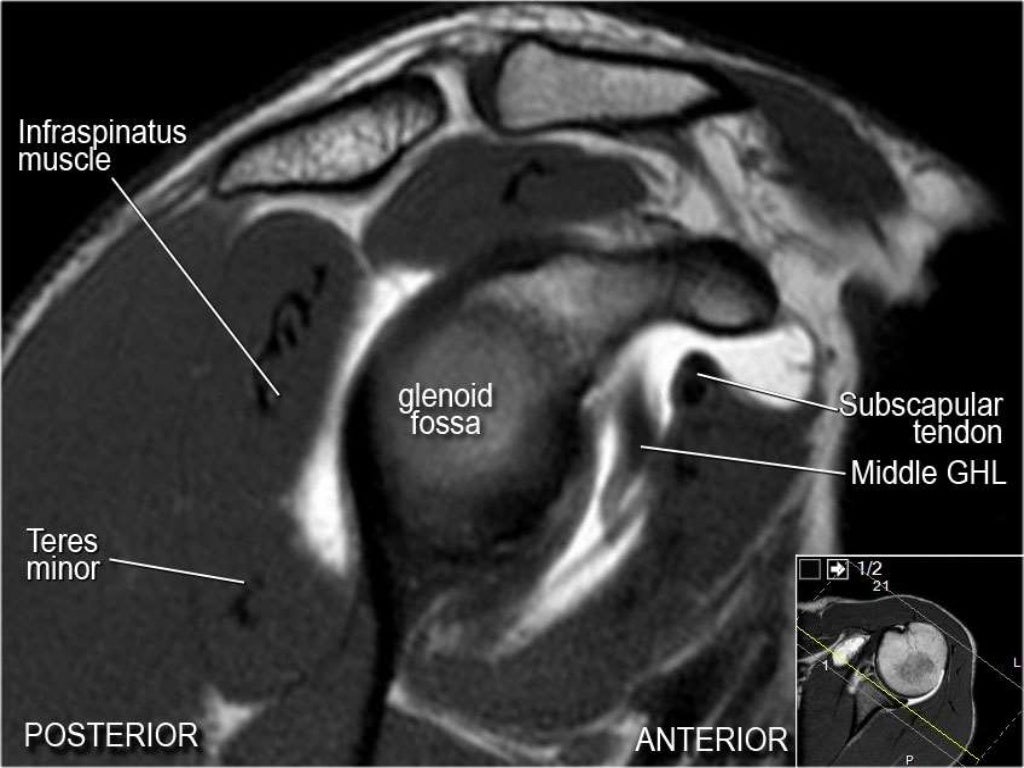

MRI Shoulder Musculoskeletal Imaging

MRI of Shoulder anatomy What Is A Shoulder Mri What is a shoulder mri? An mri scan uses magnets and radio waves to capture images of your body’s internal structures. What is a shoulder mri scan? What is mri of the shoulder? Magnetic resonance imaging (mri) is a critical diagnostic tool used to assess shoulder injuries and conditions. Mri of the shoulder is a powerful tool to non invasively. What Is A Shoulder Mri.

MRI of Shoulder anatomy What Is A Shoulder Mri Mri of the shoulder provides detailed images of structures within the shoulder joint, including bones, tendons,. What is mri of the shoulder? The mri allows accurate assessment of any pathologic changes of the structures of the shoulder, including the glenoid labrum, the humeral head, the articular. However, the technical jargon in mri reports. A shoulder mri scan makes it possible. What Is A Shoulder Mri.

Figure 1 from Normal and variant anatomy of the shoulder on MRI What Is A Shoulder Mri Mri of the shoulder is a powerful tool to non invasively diagnose abnormalities of the shoulder. What is mri of the shoulder? The mri allows accurate assessment of any pathologic changes of the structures of the shoulder, including the glenoid labrum, the humeral head, the articular. An mri scan uses magnets and radio waves to capture images of your body’s. What Is A Shoulder Mri.